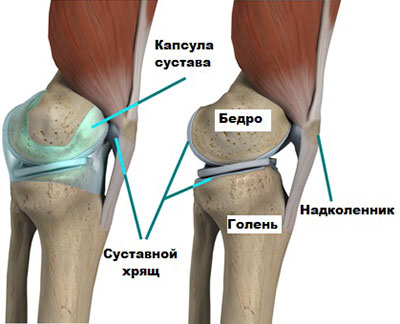

Сустав, образующий колено, сформирован верхним участком большеберцовой и нижним фрагментом бедренной костей, надколенником (одним из наиболее крупных сесамовидных костных образований), а также окружающими их мышечными тканями и сухожилиями.

Сустав, образующий колено, окружен содержащей особую анатомическую жидкость синовиальной капсулой, обеспечивающей смазку всех его элементов.

Здесь важно отметить наличие в суставе менисков – латерального, размещенного на наружной его стороне, а медиального, расположенного на наружной части. Данные хрящевые образования выполняют амортизирующую функцию, плавно распределяя нагрузку, исходящую от колена при совершении практически всех видов движений.

Хрящевая ткань, расположенная в суставе колена, обеспечивает скольжение костных участков между собой. В свою очередь мениск обеспечивает защиту хряща от чрезмерного давления, исключая, тем самым, возникновение повреждений и, как следствие, развитие артроза.